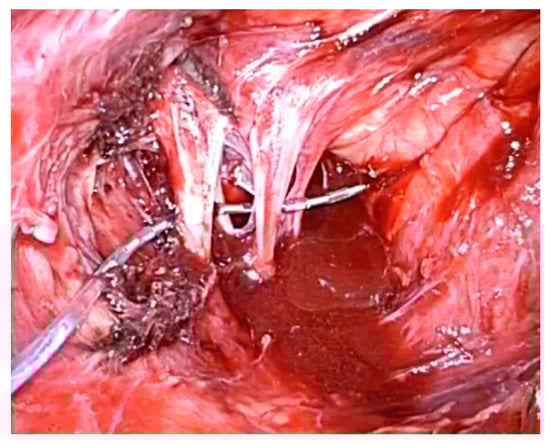

- Possover, M. Laparoscopic therapy for endometriosis and vascular entrapment of sacral plexus. Fertil. Steril. 2011, 95, 756–758. [Google Scholar] [CrossRef]

- Possover, M. Five-Year Follow-Up after Laparoscopic Large Nerve Resection for Deep Infiltrating Sciatic Nerve Endometriosis. J. Minim. Invasive Gynecol. 2017, 24, 822–826. [Google Scholar] [CrossRef] [PubMed]